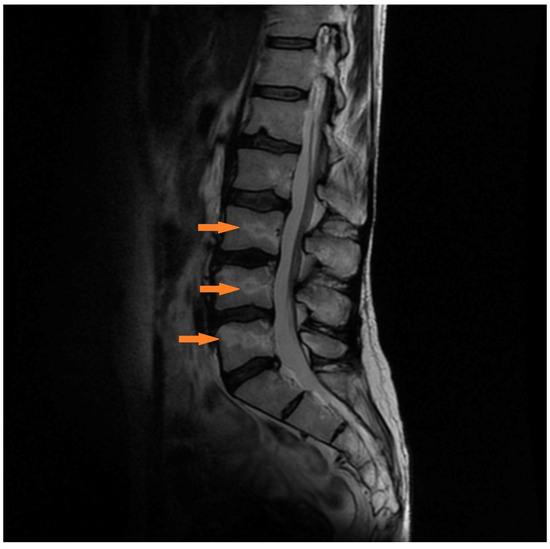

3.1.3. Case 3 (Patient No. 7)

| 7 | lumbar spine | 14 | no | 2 | 8 | 8 | 1 |